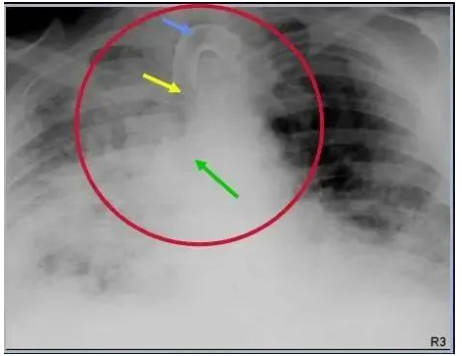

图:正常气管切开术后气管插管,蓝箭-切口,黄箭-气管插管末端;绿箭-气管隆突。